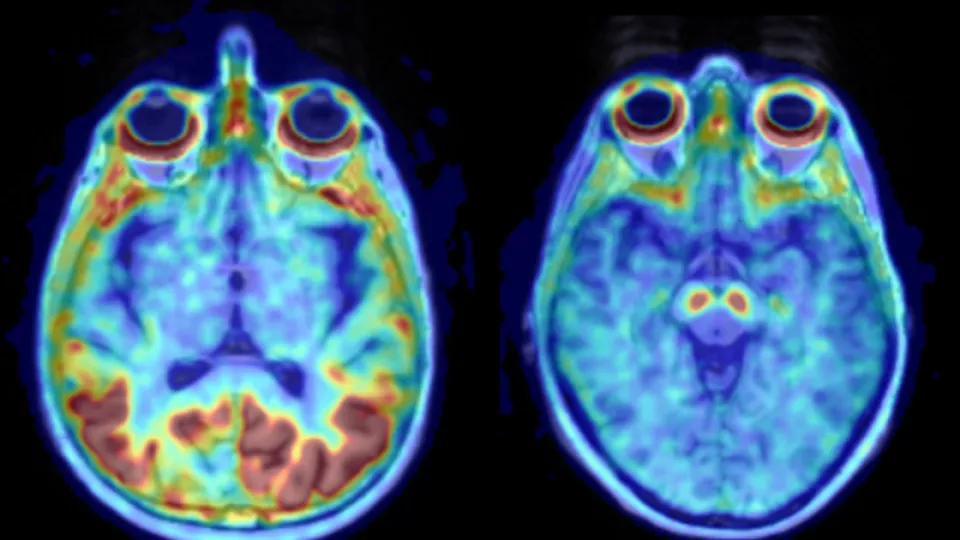

Women Accumulate Alzheimer’s-Related Protein Faster

Alzheimer’s disease seems to progress faster in women than in men.

The protein tau accumulates at a higher rate in women, according to research from Lund University in Sweden. The study was recently published in Brain.

Over 30 million people suffer from Alzheimer’s disease worldwide, making it the most common form of dementia. Tau and beta-amyloid are two proteins known to aggregate and accumulate in the brain in patients with Alzheimer’s.

The first protein to aggregate in Alzheimer’s is beta-amyloid. Men and women are equally affected by the first disease stages, and the analysis did not show any differences in the accumulation of beta-amyloid. Memory dysfunction arises later, when tau starts to accumulate. More women than men are affected by memory problems due to Alzheimer’s, and it was for tau that the researchers found a higher rate of accumulation in women.

“Tau accumulation rates vary greatly between individuals of the same sex, but in the temporal lobe, which is affected in Alzheimer’s disease, we found a 75% higher accumulation rate in women as a group compared to men,” explains Ruben Smith, first author of the study.